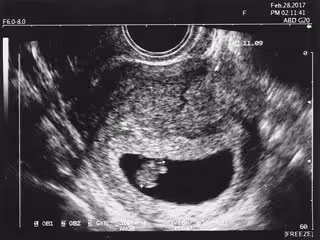

Los pulmones y las placentas de los fetos en el útero, tras 11 semanas después de la concepción, ya muestran un microbioma establecido, lo que sugiere que las bacterias pueden colonizar los pulmones mucho antes del nacimiento, según ha probado un estudio de la Universidad de Alabama en Birmingham (Estados Unidos).

En el nuevo estudio, se recogieron 31 muestras de tejido pulmonar, placentario e intestinal de fetos de entre 11 y 20 semanas de gestación. Así, detectaron ADN bacteriano a través de un análisis dirigido del gen bacteriano para el ARN ribosomal 16S, que es un método estándar para distinguir diferentes taxones microbianos. El análisis inicial del 16S mostró 48 taxones únicos en las muestras de pulmón, 11 taxones únicos en las muestras de placenta y 24 taxones compartidos.

El análisis 16S de las mismas muestras mostró dos grupos separados de microbiomas pulmonares de fetos humanos, basados en la edad del feto: un grupo entre las 11 y 15 semanas de gestación, y el otro entre las 16 y 20 semanas de gestación. Además, los dos grupos de edad gestacional mostraron un cambio significativo en la diversidad microbiana con el tiempo.